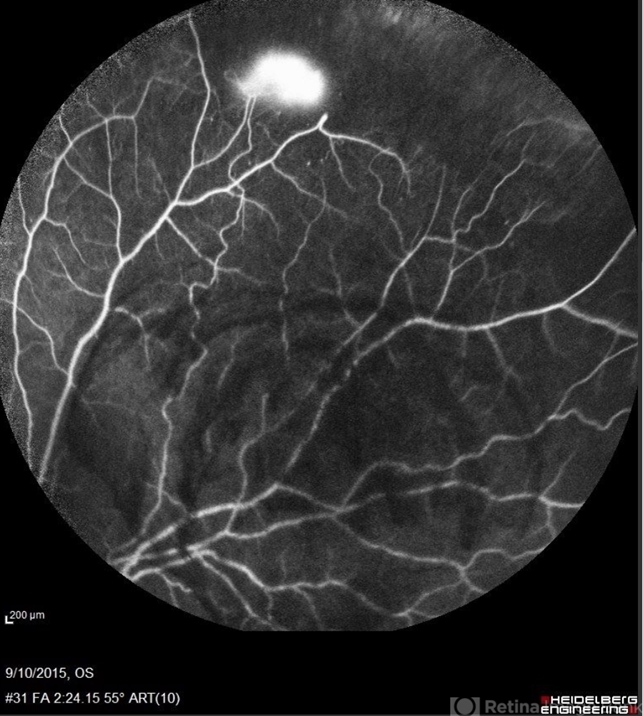

sickle cell retinopathy, peripheral retinal neovascularization, sea fan

Angiography showed normal vessels posteriorly but severe capillary drop out throughout the periphery OU with scattered severe neovascularization at the edge of the capillary drop out peripherally.